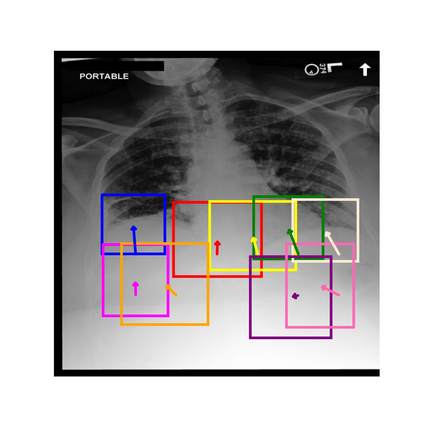

To address these issues, we propose a novel Adaptive patch-word Matching (AdaMatch) model to correlate chest X-ray (CXR) image regions with words in medical reports and apply it to CXR-report generation to provide explainability for the generation process. AdaMatch exploits the fine-grained relation between adaptive patches and words to provide explanations of specific image regions with corresponding words. To capture the abnormal regions of varying sizes and positions, we introduce the Adaptive Patch extraction (AdaPatch) module to acquire the adaptive patches for these regions adaptively. In order to provide explicit explainability for CXR-report generation task, we propose an AdaMatch-based bidirectional large language model for Cyclic CXR-report generation (AdaMatch-Cyclic). It employs the AdaMatch to obtain the keywords for CXR images and `keypatches' for medical reports as hints to guide CXR-report generation. Extensive experiments on two publicly available CXR datasets prove the effectiveness of our method and its superior performance to existing methods.